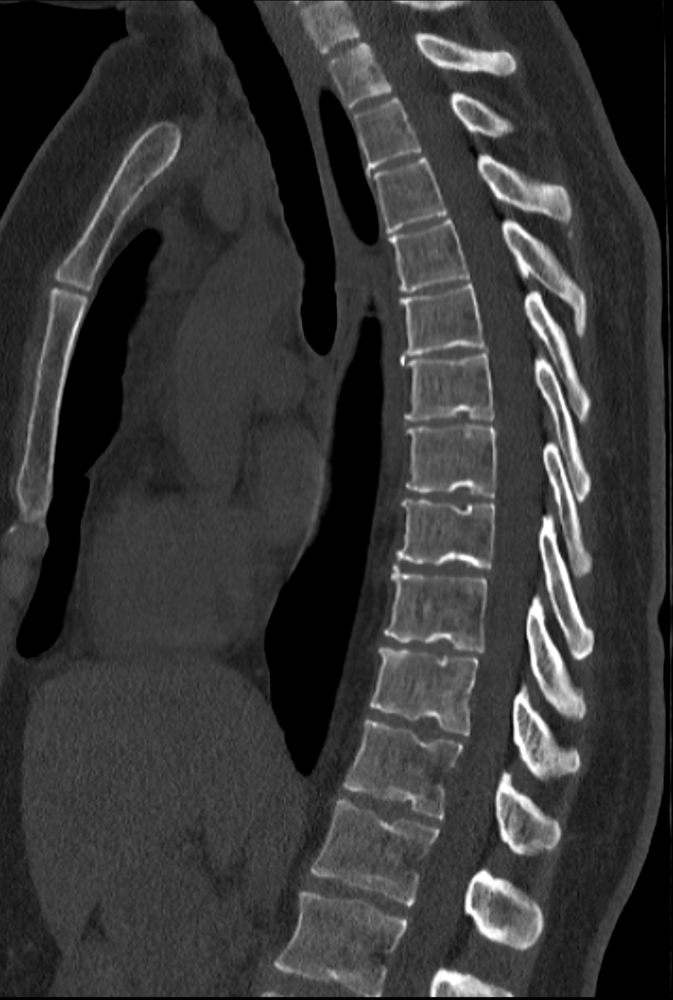

CT aller Gelenke und der Wirbelsäule

Die Computertomographie (CT) der Gelenke und der Wirbelsäule ist ein bewährter diagnostischer Ansatz, um Knochen- und Gelenkstrukturen zu beurteilen. Die Untersuchung zielt vor allem darauf ab, die knöchernen Anteile der Gelenke und Wirbelsäule detailliert zu visualisieren, um Erkrankungen, Verletzungen, Entzündungen oder andere medizinische Probleme zu identifizieren. Abhängig von den individuellen Symptomen und der klinischen Indikation kann sie zur Diagnose von Beschwerden in verschiedenen Bereichen des Körpers verwendet werden, so etwa Schultern, Ellenbogen, Hüften, Knien und der gesamten Wirbelsäule. Damit unterstützt die Computertomographie beispielsweise die Diagnose von Arthrosen, Bandscheibenvorfällen, Frakturen oder Tumoren. Dem Arzt bietet das Verfahren somit eine wichtige Grundlage für die Diagnose und Behandlungsplanung.